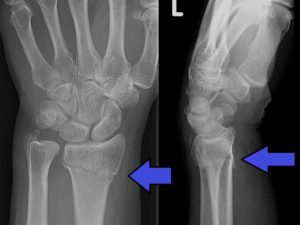

Повреждение подразделяется на 2 вида в зависимости от положения кисти на момент падения: сгибательное и разгибательное.

Разгибательный перелом Колеса возникает вследствие приземления на разогнутую кисть. Дистальный (нижний) костный отломок под влиянием задней группы мышц предплечья оказывается смещенным к тыльной поверхности конечности. Этот вариант встречается чаще.

Причина сгибательного перелома Смита – падение на вытянутую и согнутую в ладони кисть. Для повреждения характерно смещение дистального отломка к ладонной, или внутренней поверхности предплечья. При проникновении отломков в полость лучезапястного сустава травму относят к внутрисуставной. Интересная статья по теме перелом костей предплечья.

Перелом лучевой кости в типичном месте подразделяют на сгибательный (со смещением обломка к тыльной стороне ладони) и разгибательный (с характерным смещением костного фрагмента к лучевой стороне).